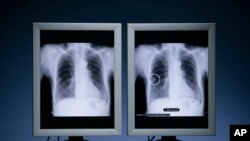

FILE - Riverain's OnGuard Chest X-ray CAD (computer-aided detection) technology detects suspicious nodules that may be early-stage lung cancer, leading to improved patient survival rates, Nov. 20, 2007. (PRNewsFoto/Cleveland Clinic and Riverain Medical)